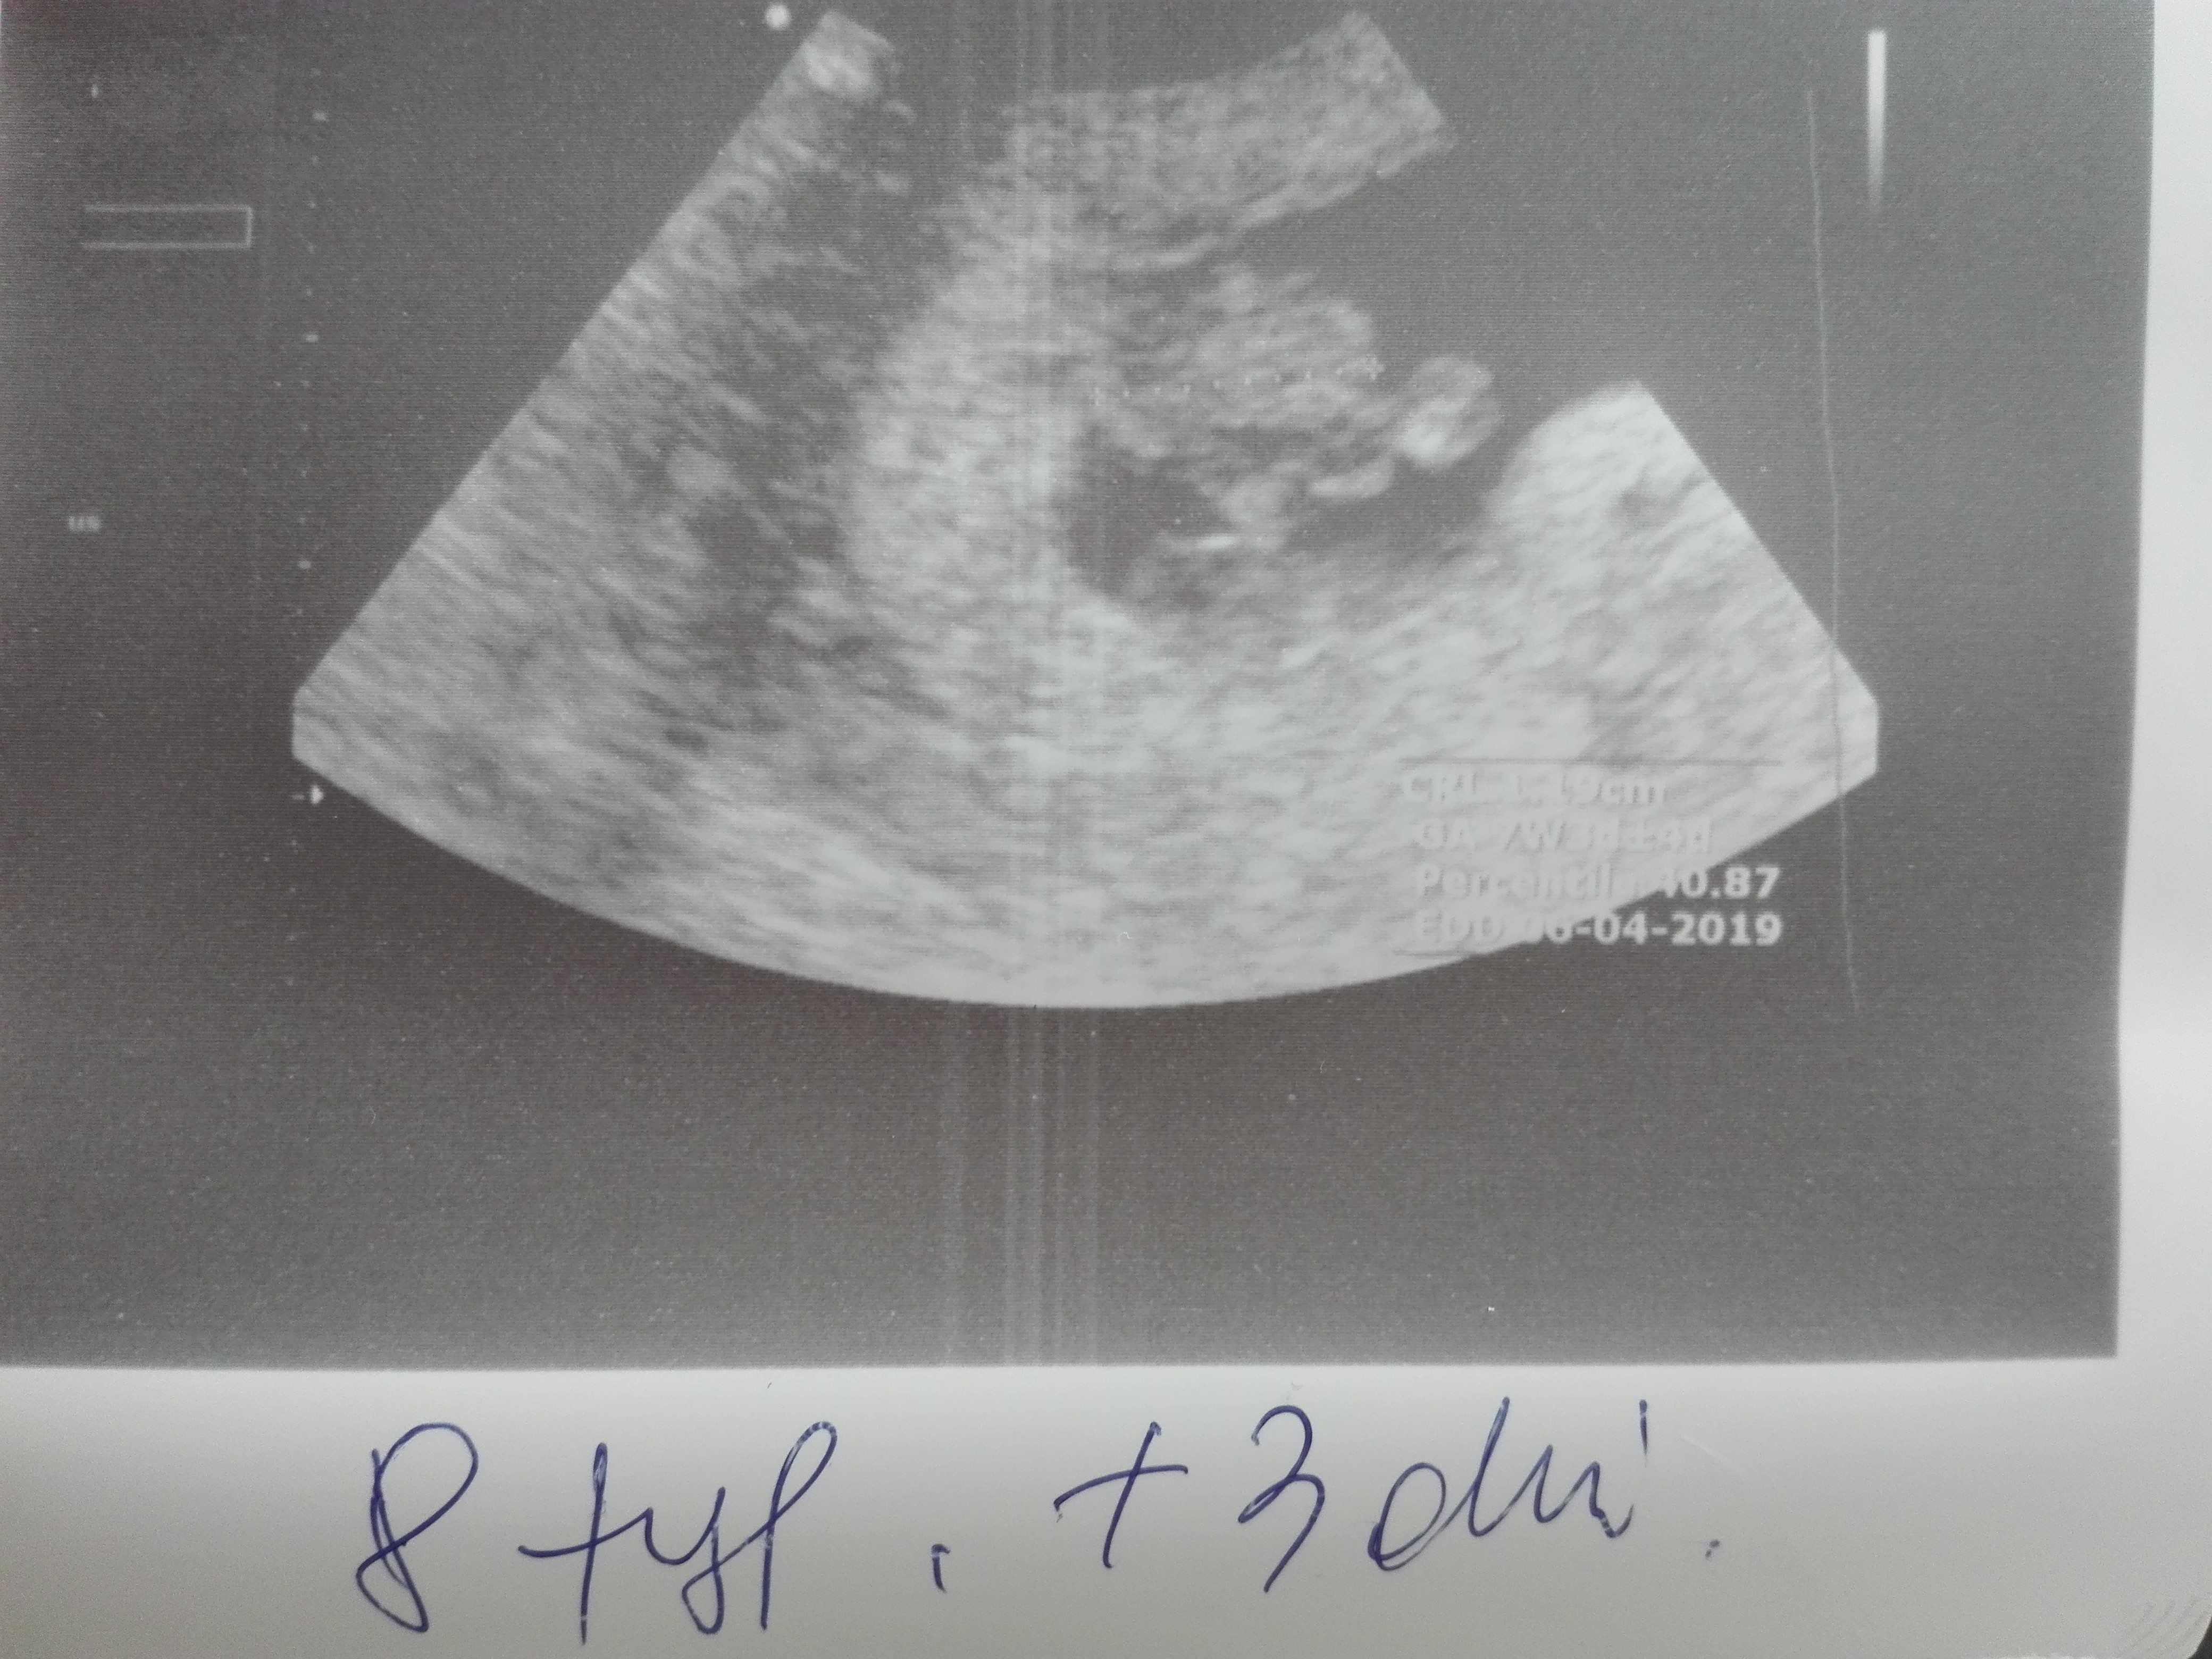

Jestem po pierwszym USG:) serduszko bije 156 uderzeń na minute, maleństwo ma 1,26cm, wszystko w jak najlepszym porządku:D

Załączniki

• IMG_20180820_184438.jpg

IMG_20180820_184438.jpg

50,7 KB · Wyświetleń: 253

• IMG_20180820_193057-1512x1368.jpg

IMG_20180820_193057-1512x1368.jpg

720,3 KB · Wyświetleń: 253